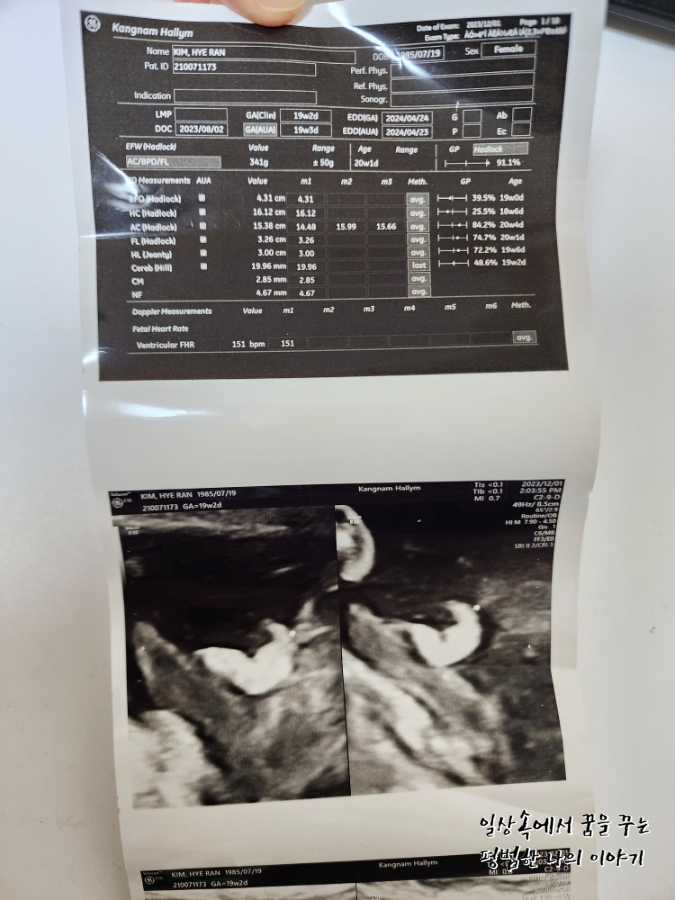

BPD(Biparietal Diameter, 위에서 볼 때 태아 머리 단면의 가장 긴 길이): 4.31cm

HC(Head Circumference, 태아 머리둘레): 16.12cm

AC(Abdominal Circumference, 배 둘레): 15.38cm

EDD(Expected Date of Delivery, 출산 예정일): 2024년 4월 24일

FL(Femur Length, 허벅지뼈 길이): 3.26cm

GA(Gestational Age, 임신 주차): 19주 차 2일

EFW(Estimated Fatal Weight, 태아 예상 체중)=EBW(Estimated Body Weight): 317g

Cereb(Cerebelleum, 소뇌 크기): 19.96mm

FHR(Fetal Heart Rate, 심장박동 수): 151bpm

CL(Cervical Length, 자궁경부 길이): 정상

AF(Amniotic Fluid, 양수): 정상